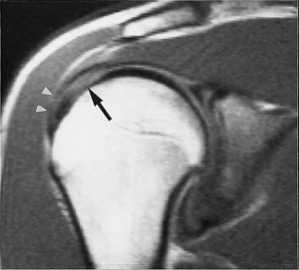

МРТ плечевого сустава с подавлением сигнала от жира. Т2-взвешенная корональная МРТ. Перелом большого бугорка (стрелка).

При МРТ плечевого сустава косвенным признаком разрыва вращательной манжеты служит высокий сигнал на Т2-взвешенных от поверхности сустава до субакромиальной (субдельтовидной) сумки. Частичные разрывы чаще всего по передней поверхности сухожилия м.supraspinatus, реже примыкая к большой бугристости или сухожилия м. infraspinatus.